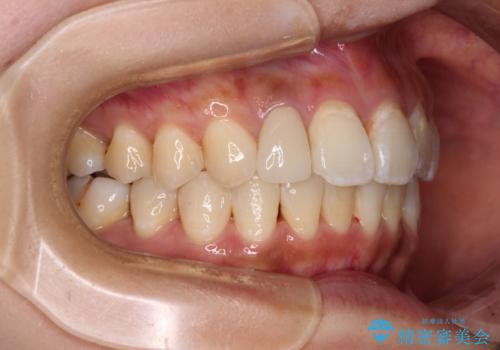

デコボコで磨きにくい前歯をスッキリと インビザライン矯正

- 虫歯が多く、磨きにくい歯並びを改善したいとのことで来院された患者様です。

歯列は叢生が認められる程度でしたが、やや前突感があったので、少しでも口が閉じやすくなるように仕上げる方針としました。

神経を取り除かれている歯3本以外にも虫歯が認められたため、事前に処置を行い、インビザラインにて矯正治療を行うこととしました。

歯磨きしやすくなるとともに、飛び出していた前歯も引っ込めて整えることができました。